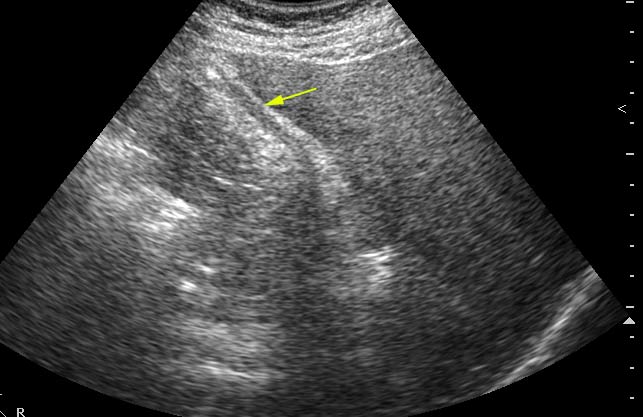

Молодой мужчина с болями в эпигастральной области.

Осматривался дважды натощак. Выявлены изменения желчного пузыря.

Печень, селезенка при УЗИ не изменены.

Думаю,что это не просто пустой ж.пузырь,он содержит гиперэхогенное включение в середине,повторяющее форму ж.пузыря и дающее позадиакустическую тень.Возможна кальцифицированная аскарида

Нефункционирующий желчный пузырь содержит гиперэхогенное включение.

Первый ж.пузырь удален, клинический диагноз "сморщенный желчный пузырь, ЖКБ", гистология - фиброз стенок желчного пузыря.